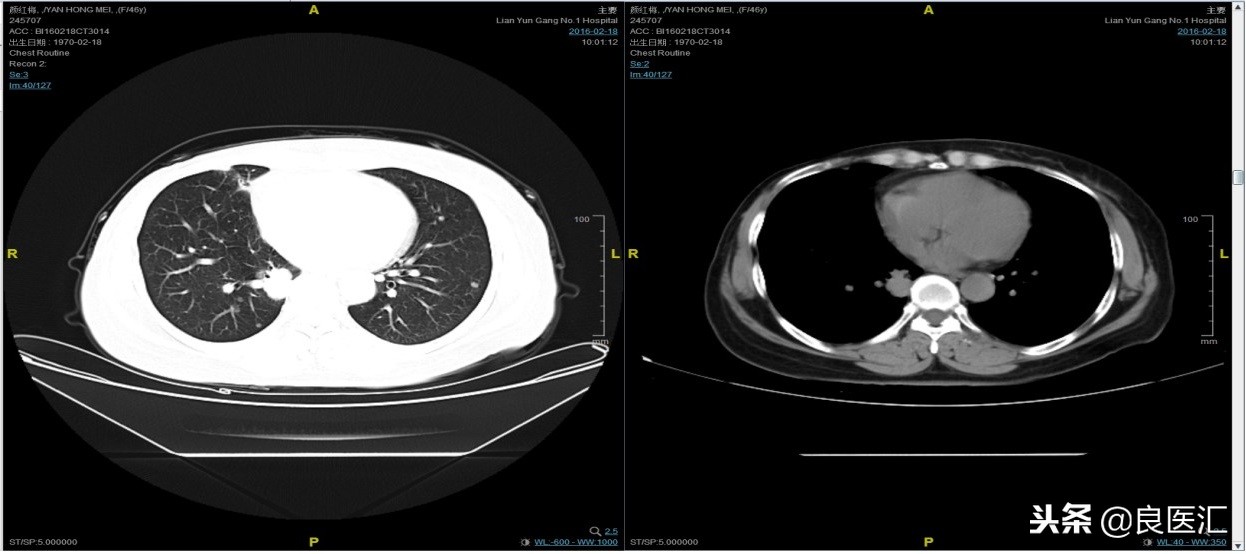

随访至2016-2-18,肺部病灶进展,肺内转移病灶增多。PFS2=10个月。

从2016-2-19开始给予紫杉醇+曲妥珠单抗治疗,紫杉醇240mg,3周重复,曲妥珠单抗330mg三周重复。患者末次应用曲妥珠单抗和紫杉醇时间为2016-6-24,紫杉醇共应用4周期。

期间2016-4-22复查CT如下:

2016-7-5化疗结束后复查CT,疗效评价稳定。